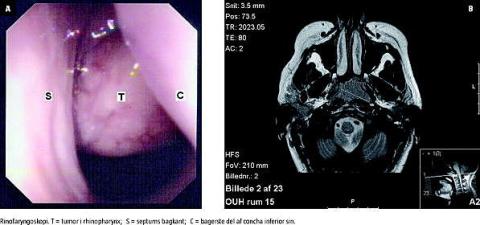

En 22-årig kvinde blev henvist akut fra egen læge til en øre-næse-hals-afdeling grundet kraftig venstresidig epistaxis. Patienten var gravid i uge 38. Hun havde desuden nedsat luftpassage i venstre næsebor og havde haft venstresidig hørenedsættelse gennem to uger. Efter oprensning og hæmostase med ætsning af næseslimhinden i overfladeanæstesi fandt man ved rinofaryngoskopi med optik en prominerende tumor i rhinopharynx (Figur 1A). Tympanometri viste en flad kurve, hvilket var foreneligt med væske i venstre mellemøre. Ved otomikroskopi fandt man væske bag trommehinden, hvilket tyder på tubaokklusion. Biopsi fra tumoren i næsesvælget viste adenokarcinom, lymfoepitelialt karcinom. Magnetisk resonans-skanning af hoved/hals viste en 2,2 × 3,2 × 2,3 cm stor tumor i rhinopharynx (Figur 1B), samt en 2,6 cm stor lymfeknude på venstre side af halsen, sidstnævnte bekræftet ved ultralyd af collum. Røntgen af thorax viste normale forhold. Fundene svarede således til T1 N1 M0 rhinopharynxcancer. Efter konference med en onkolog og en obstetriker afventede man normal fødsel, hvorpå patienten påbegyndte radiokemoterapi (66 Gy/33 fraktioner/cisplatin). Ved klinisk etårskontrol inkl. fiberskopi og ultralyd af halsen var patienten recidivfri.

Konklusion: Såvel epistaxis, ensidig sekretorisk otitis media som nasalstenose skal ved vedvarende symptomer udredes med fiberskopisk undersøgelse af næse og svælg for at udelukke tumor.